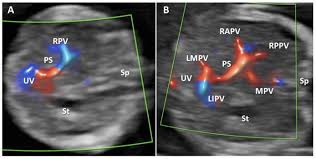

- 간: 형태 이상, 지방간 여부, 간경화 진행도, 종양, 낭종, 혈류 상태

- 복부 대동맥 등 주요 혈관: 동맥류, 혈류 장애

- 간경화 및 문맥압 항진 증상